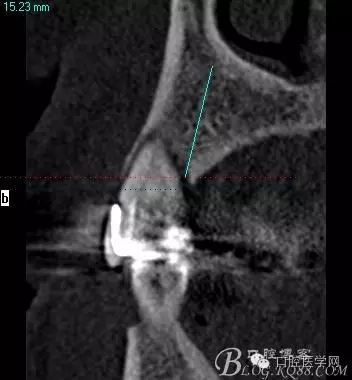

植入當然毫無難度可言,只是想術后的方向更加賞心悅目而已,14稍微有點難度,記住 上頜牙顎側(cè)骨板肯定比頰側(cè)硬多了。 所以(特別是柱行種植體柱行鉆)永遠要記住上頜牙備洞過程是會往頰側(cè)慢慢偏出去的 。(根型植體菱形鉆相對這個問題好控制點)所以我們第一鉆定位要比預計的中心點更加靠顎側(cè)多點 ,到底多多少,這個很難把握,感覺吧 。 上圖我畫了小圈的地方,是種植體離頰側(cè)和近中骨壁的距離空腔 (這個情況可以考慮植骨或者不植骨 我選擇了自體骨)。

頰顎向的方向也很理想 箭頭所示 空間填滿了自體骨